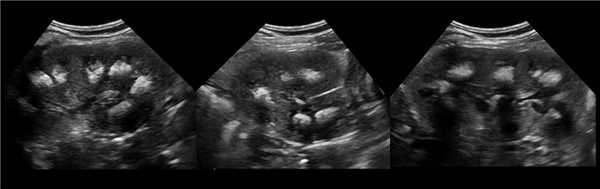

Клинический пример из второй группы. Пациент К. перенес операцию пересадки почки от живого родственного донора. Трансплантат в левой подвздошной области. Индекс резистентности в междольковых артериях составил 0,70 (рис. 5). В сегментарных артериях индекс резистентности составил 0,66 (рис. 6). Показатели жесткости паренхимы почечного трансплантата при режиме УЭСВ составили от 31,6 до 36,9 кПа (рис. 7-9).

Рисунок 7. Исследование в режиме ультразвуковой эластографии сдвиговой волны у пациента К.: жесткость паренхимы в зоне медиального края почечного трансплантата 36,9 кПа

Рисунок 8. Исследование в режиме ультразвуковой эластографии сдвиговой волны у пациента К.: жесткость паренхимы в зоне нижнего полюса почечного трансплантата 34,7 кПа

Рисунок 9. Исследование в режиме ультразвуковой эластографии сдвиговой волны у пациента К.: жесткость паренхимы у верхнего полюса почечного трансплантата 31,6 кПа